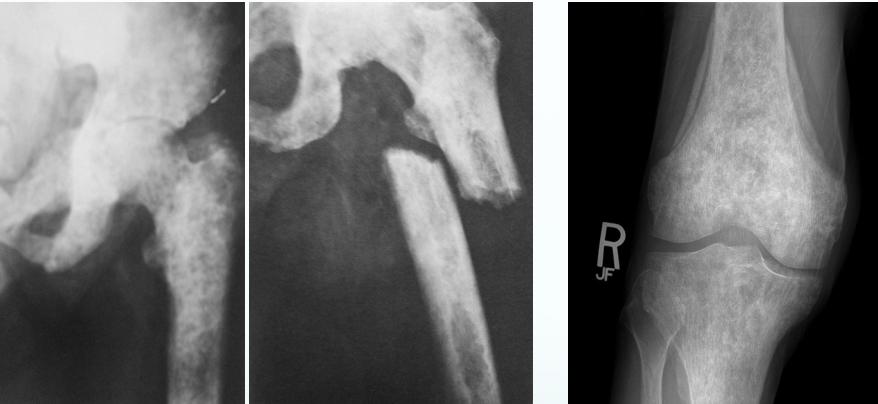

- X-ray:

- Osteolytic, moth-eaten

- Osteoblastic in ca prostate

Specific Examples